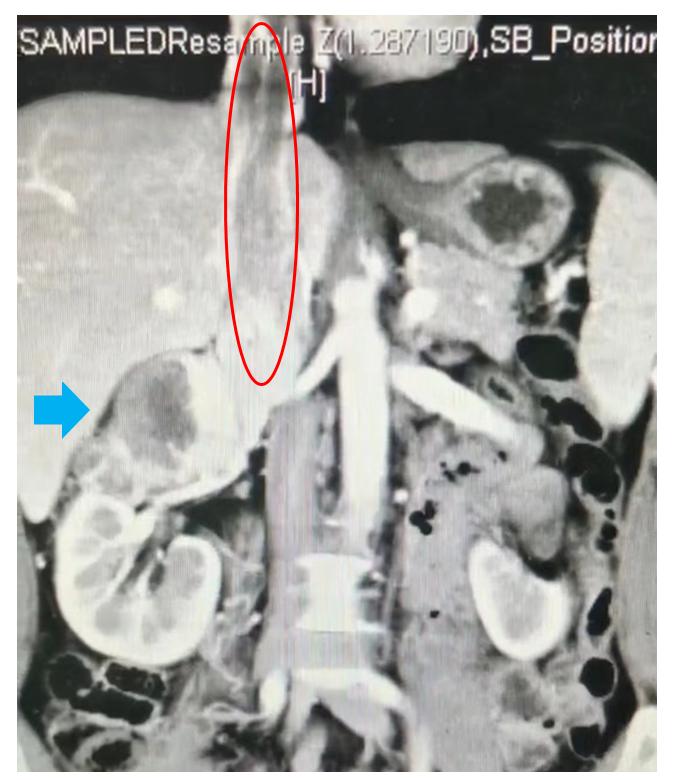

癌栓从肾脏发出,向上进入心脏。蓝色箭头所示为肾癌,红色圈内为肾癌长出进入静脉内的癌栓

时间回到两个月前,一次普通的体检给赵先生的生活蒙上了一层阴影。体检发现,赵先生的右肾上出现了一个直径约8cm的巨大肿瘤,而更为可怕的是,肿瘤突破了肾脏的界限,沿着肾静脉一路向上生长,竟进入了赵先生的心脏内,整个肿瘤长达20cm,其中侵入心脏内部分达5cm。赵先生被诊断为肾癌合并下腔静脉癌栓。